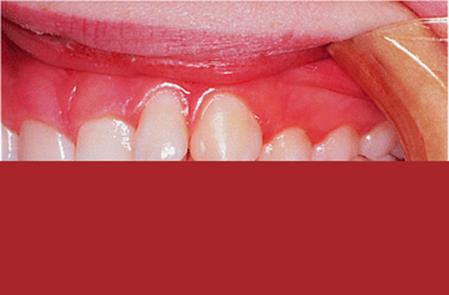

18.3.2. Class II division 2

Treatment of a Class II division 2 malocclusion can be prolonged and difficult because correction of the incisor relationship requires reduction of the overbite and reduction of the inter-incisal angle to ensure stability of the result (Chapter 10). This can be done with fixed appliances, but the treatment is extensive as it involves correcting the retroclination of the upper incisors by moving their apices palatally, thus reducing the inter-incisal angle.

An alternative approach is to correct the upper incisor angulation by moving their crowns labially, which is often straightforward using a removable appliance. The resulting increased overjet and the deep overbite can then be corrected using a functional appliance. This method is particularly appropriate where the lower arch is well aligned. The retroclined upper incisors are often crowded, but this resolves as they are tilted labially into a larger arc. The malocclusion has then been changed from Class II division 2 to a Class II division 1 with aligned arches, which is ideal for treatment with a functional appliance (Fig. 18.3).

Fig. 18.3. (a) Class II division 2 malocclusion with well-aligned lower arch; (b) upper removable appliance to expand the arch and procline the upper incisors; (c) activator appliance in place; (d) some overcorrection was achieved.